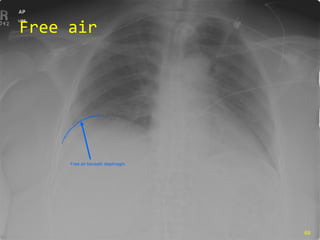

Free air Free air beneath diaphragm

Air under the diaphragm